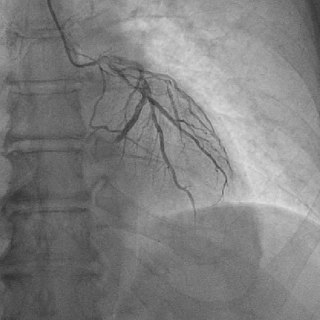

Так виглядає динаміка NSTEMI 1. Біль за грудиною + 2. Зміни на ЕКГ (перше фото: депресія до 1 мм V4-V6, друга плівка н...